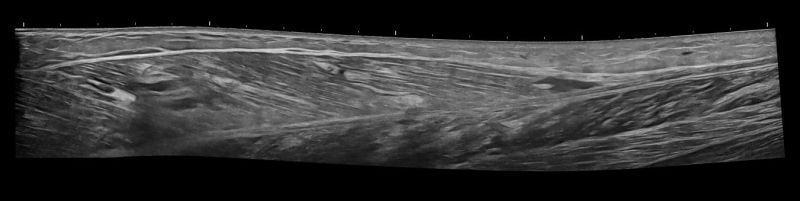

- Κατηγοριοποίηση (Grading) Θλάσεων Μυών: Το Υπερηχογράφημα Μυών μπορεί να αποτελέσει ιδανικό εργαλείο για την ανίχνευση και εκτίμηση της έκτασης μυϊκών θλάσεων μετά από τραυματισμό ή άλλα μυϊκά προβλήματα.

- Διάγνωση Μυϊκών Βλαβών: Το Υπερηχογράφημα Μυών επιτρέπει την αναγνώριση μυϊκών παθήσεων όπως τα αιματώματα, τα λιπώματα, τα νεοπλάσματα και η σημειολογία ασβεστοποιού μυοσίτιδας.

- Δυναμική Εξέταση: Με το Υπερηχογράφημα Μυών μπορούμε να παρατηρήσουμε τους μύες κατά τη διάρκεια διαφόρων κινήσεων, κάτι που μας επιτρέπει να ανιχνεύσουμε μυϊκές ανωμαλίες που ενδέχεται να μην είναι ορατές σε στατικές εικόνες.